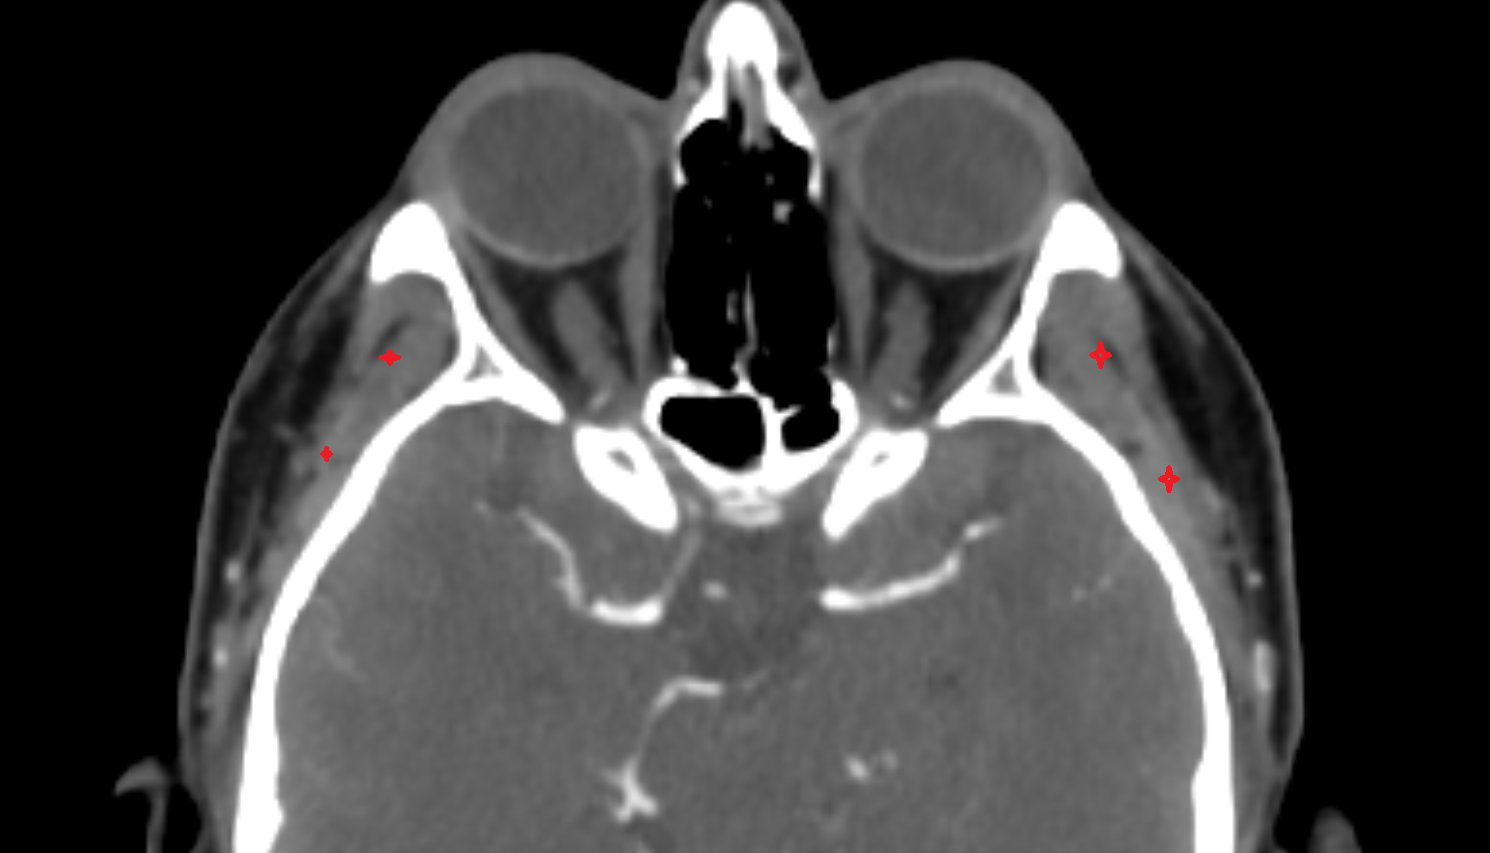

- Retrobulbar fat